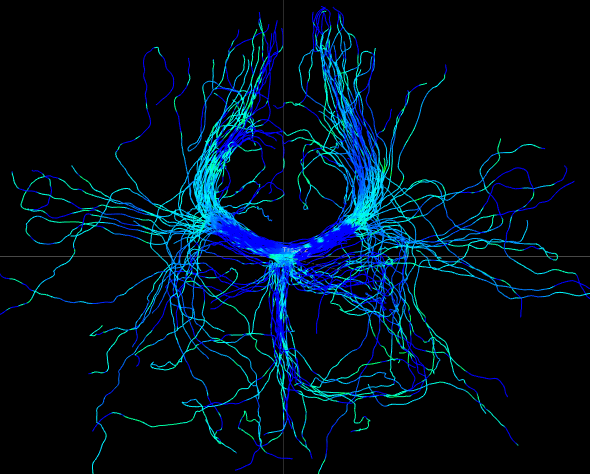

We perform whole brain streamline tractography on the estimated fODF field using mrtrix (Tournier et al., 2012) 888http://www.mrtrix.org/. The voxels with GFA larger than are used as seed voxels to generate tracts by using tckgen in mrtrix. All other parameters are default parameters in mrtrix. The obtained fiber tracts are then visualized by using trackvis 999http://trackvis.org. Fig. 14 and 15 demonstrate the tracts respectively cross two given ball ROIs. The tracts are colored by using the proposed six scalar indices. Note that the proposed scalar indices are calculated based on estimated fODFs, not based on fiber tracts. It can be seen that 1) OO is high in areas with well aligned fibers, while OD is high in crossing areas and distortion areas; 2) distortion indices are low when fibers are well aligned; 3) the total distortion index is high in areas with highly curved fibers or crossing fibers. 4) although splay, bend, twist indices may be separable (e.g., one is large while another one is close to zero) in synthetic data, in real data, these three types of distortions normally occur together, especially for bending and splaying. 5) the ROI in Fig. 14 is the crossing area of the Corpus Callosum and the Fornix, where all distortion indices have high values, especially for twist and total distortion indices. This finding agrees with Fig. 12.

Non-negative spherical deconvolution (NNSD) (Cheng et al., 2014) is performed to estimate non-negative fiber ODFs from three-shell DWI data. NNSD works for multi-shell data. It is more robust to noise, and the obtained fiber ODFs (fODFs) in isotropic regions are closer to the isotropic spherical PDF, compared with conventional constrained spherical deconvolution (Tournier et al., 2007). After obtaining the fODFs by NNSD, the peaks are detected from the estimated fODFs with GFA larger than , as described in Section 3.4. OO and OD are calculated from the spherical harmonic representation of fODFs along their principal peaks as shown in Algorithm 1. The second row in Fig. 11 demonstrates FA from tensors estimated by DTI, OO and OD from fODFs estimated by NNSD, and the total distortion map estimated from the local orthogonal frames of fODFs. Fig. 12 and 13 show the close-up views of fODFs, local orthogonal frames, and the six proposed indices for the red and blue regions in Fig. 11, where the region shown in 12 is also visualized in the DFA pipeline in Fig. 1. The fODF glyphs are colored by using its sampled directions. The three orientations in the local orthogonal frame in each voxel are visualized by using three tubes in red, green, and blue colors respectively. There is no local orthogonal frame in some voxels because those voxels have GFA values lower than . These figures show the following: 1) OO is high in anisotropic areas with well-aligned directions, while OD is high in isotropic or crossing areas. 2) The four orientational distortion indices are low in areas with well aligned principal directions, and zero in isotropic voxels without peaks. Distortion indices are high in voxels where the principal directions in its local neighborhood change largely. 3) The central voxels in red region is the crossing area of the Corpus Callosum from left to right and Fornix that goes through the coronal slice. The twist index showed high value in this crossing area as expected.